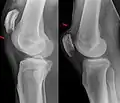

Quadriceps tendon rupture in plain X-ray -

X-ray of a tear of the patellar tendon. On the left: The kneecap is pulled up. On the right: Significant dent in the soft tissue above the kneecap. -